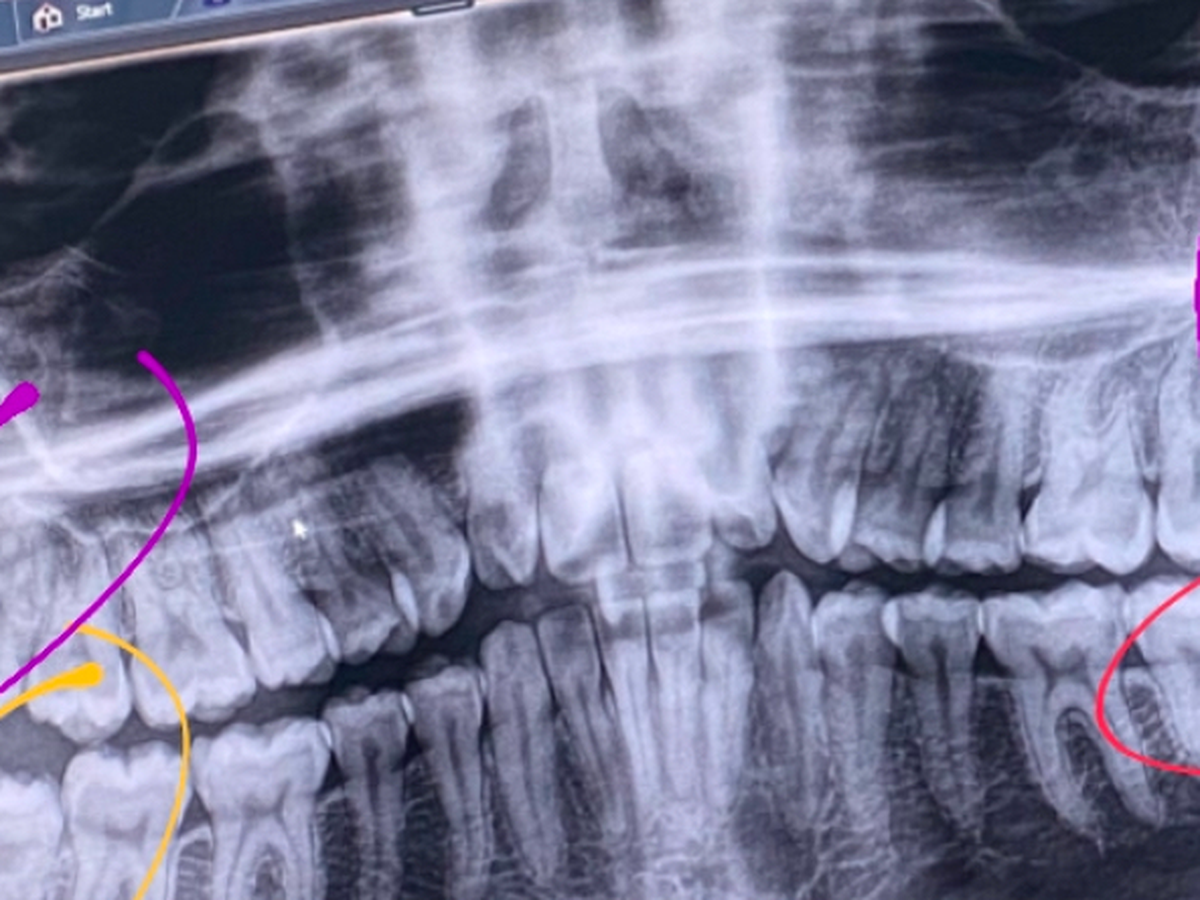

On Friday in the midst of the snowstorm I broke a tooth. Upon getting my examination on Monday I found out that I am going to need a root canal on my back left molar, and a cap on the tooth in front of it. In addition to this, it was revealed via x ray that my three remaining wisdom teeth are impacted, with the upper teeth having their roots embedded in my sinus cavity. I need to have these removed immediately, as they pose a significant risk to my overall health if they become infected or need a root canal. The initial amount I was quoted for these procedures was $7700. I am trying to raise part of this amount as I absolutely cannot afford this at all. Having an active infection is directly impacting my blood sugar and making my type 1 diabetes significantly harder to manage, so getting this taken care of as soon as possible is my top priority. Thank you for anything and everything you can give.